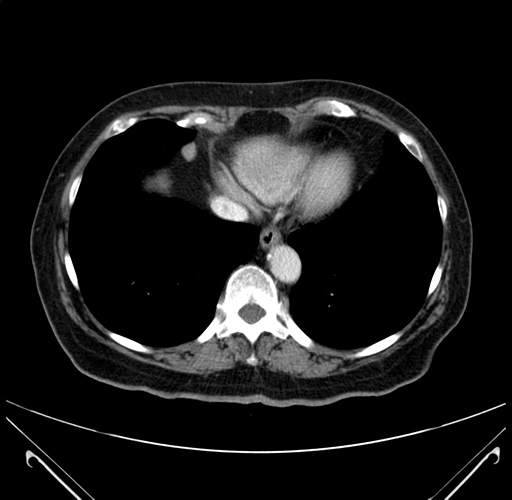

Coronal Venous